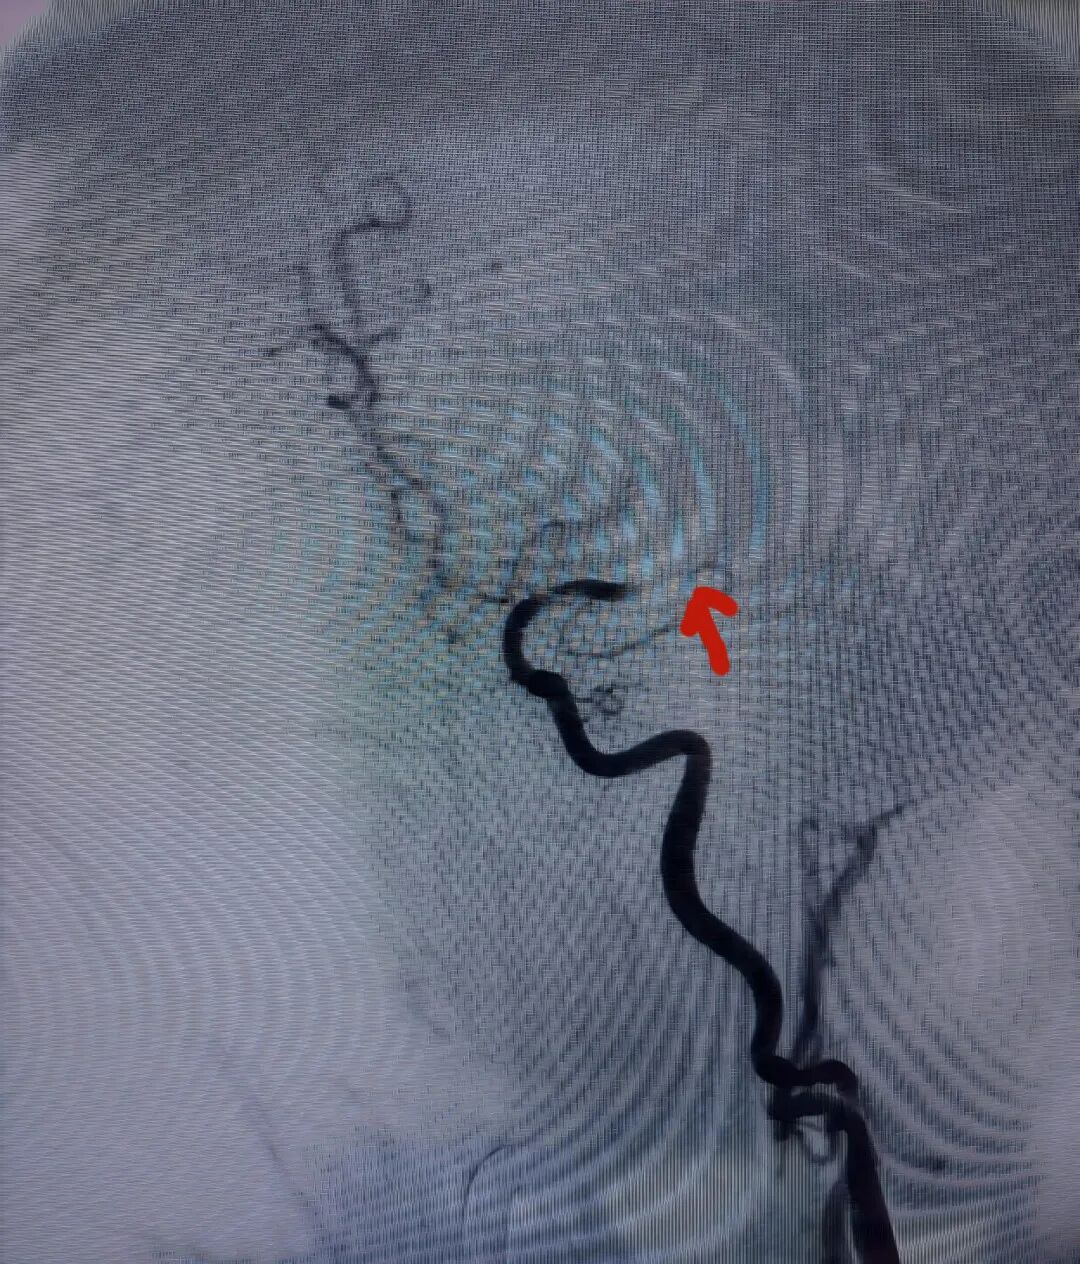

陈阿姨术前颈动脉CTA及DSA

陈阿姨术后DSA